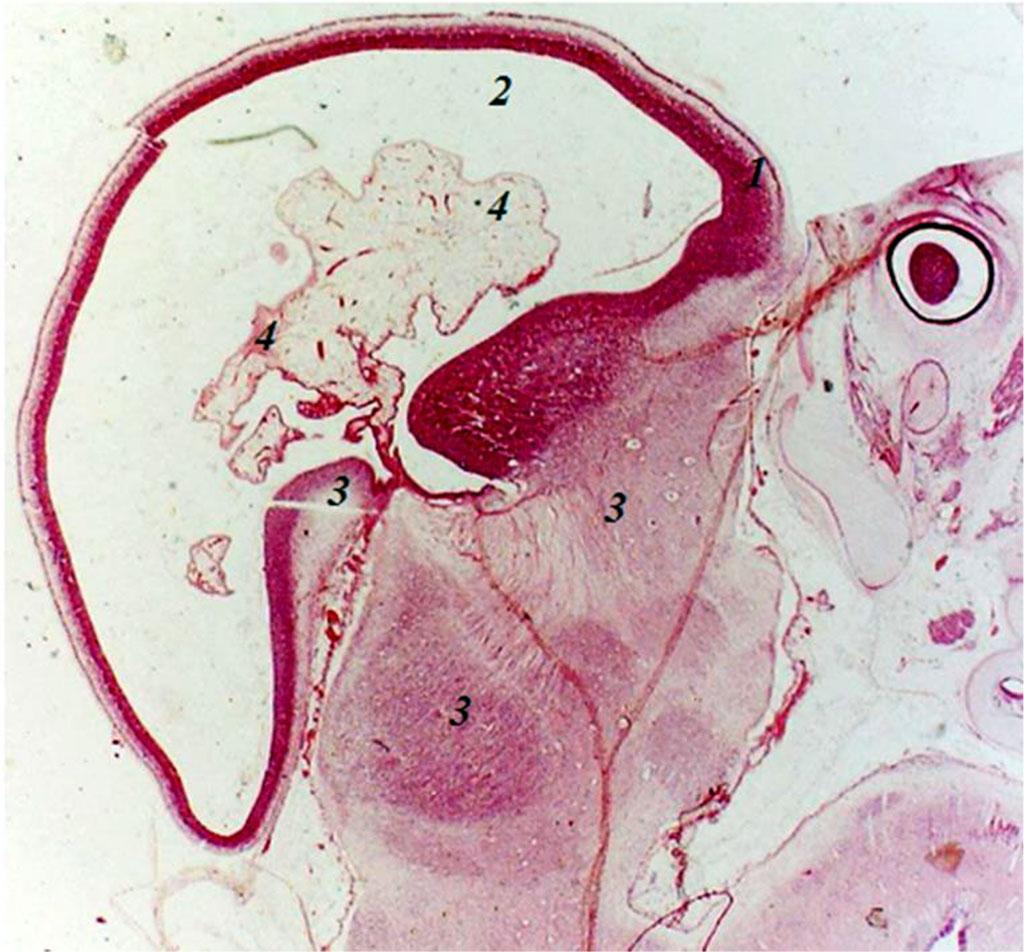

Fig. Sagittal section of the embryo of 8 weeks of intrauterine development: 1 - endbrain wall; 2 - endbrain cavity; 3 - anlages of arterial trunks; 4 - plexiform branching of arterial anlages; 5 – anlage of the eye cup. Increased by 160.

In embryos of 27 mm CRL (8 weeks of intrauterine development), the anlage of the endbrain contains an irregularly elongated cavity. In the cavity and walls (there are 3 of them) of the endbrain anlage, the anlages of the arteries are found, sometimes the anlage of the artery with elements of plexiformity is clearly detected. The cavity of the endbrain is closely adjacent to the underlying sections and that’s where the anlage of the arterial system derives from. Moreover, the anlage of this plexus is formed from the anlages of the arteries lying between the anlages of the endbrain and the underlying parts of the brain, where the anlages of the arteries are also detected. In the caudal-ventral part of the hindbrain, a cavity with two walls is revealed, with arterial anlages in its lumen. Embryos of 8 weeks of intrauterine development have anlages of both primary internal carotid arteries with an emerging plexus of anlages of branches of the primary internal carotid arteries, anlages of the primary vertebral arteries, anlages of the primary basilar artery with plexiform branching.

Embryos of 21 mm crown-rump length (CRL) (7 weeks of intrauterine development) clearly show the endbrain, interbrain, midbrain, hindbrain and spinal cord. The anlage of the endbrain contains an irregularly elongated cavity, while in the anlages of the underlying parts of the brain no cavitary formations are found. In these parts of the brain, the anlages of future arteries and arterial plexuses are determined. However, the arterial plexus anlages in the endbrain are less clear. In the anlages of the hindbrain and spinal cord, 1–2 large arteries are identified. Caudally from the endbrain and ventrally from the midbrain, but in the interbrain, the anlages of the eye cup and eye are determined. Dorsally from the eye cup, on the border of the midbrain and interbrain, the anlage of the spinal ganglion is clearly identified, with nerve trunks extending from it to the endbrain. Embryos of 7 weeks of intrauterine development have anlages of clearly defined both primary internal carotid arteries, anlages of persistent trigeminal arteries, anlages of primary vertebral arteries, anlages of the primary basilar artery (Fig.).